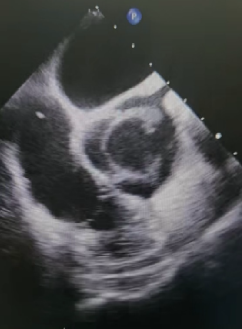

今年春节节假日第一天,当人们沉浸在团圆的喜悦中时,急诊铃声划破了节日的宁静,董亚玲医生接到紧急电话,需配合完成心脏移植供体评估获取,接到通知后她立即乘坐救护车跨市前往,术前供体评估是移植成功的关键前提,超声检查能够精准评估供心的结构、功能,排查潜在异常,为供体选择提供科学依据,为移植手术筑牢第一道防线;

与此同时,武慧蓉医生已在手术室为心脏移植受体患者行经食道超声,心脏移植术中食道超声是不可或缺的“导航仪”,通过将超声探头置入食道,可近距离获取高分辨率的心脏影像,实时监测心脏各腔室、瓣膜及血管的形态与功能,精准指导手术操作,及时发现术中心包积液、血管吻合口异常等,确保手术安全高效推进。